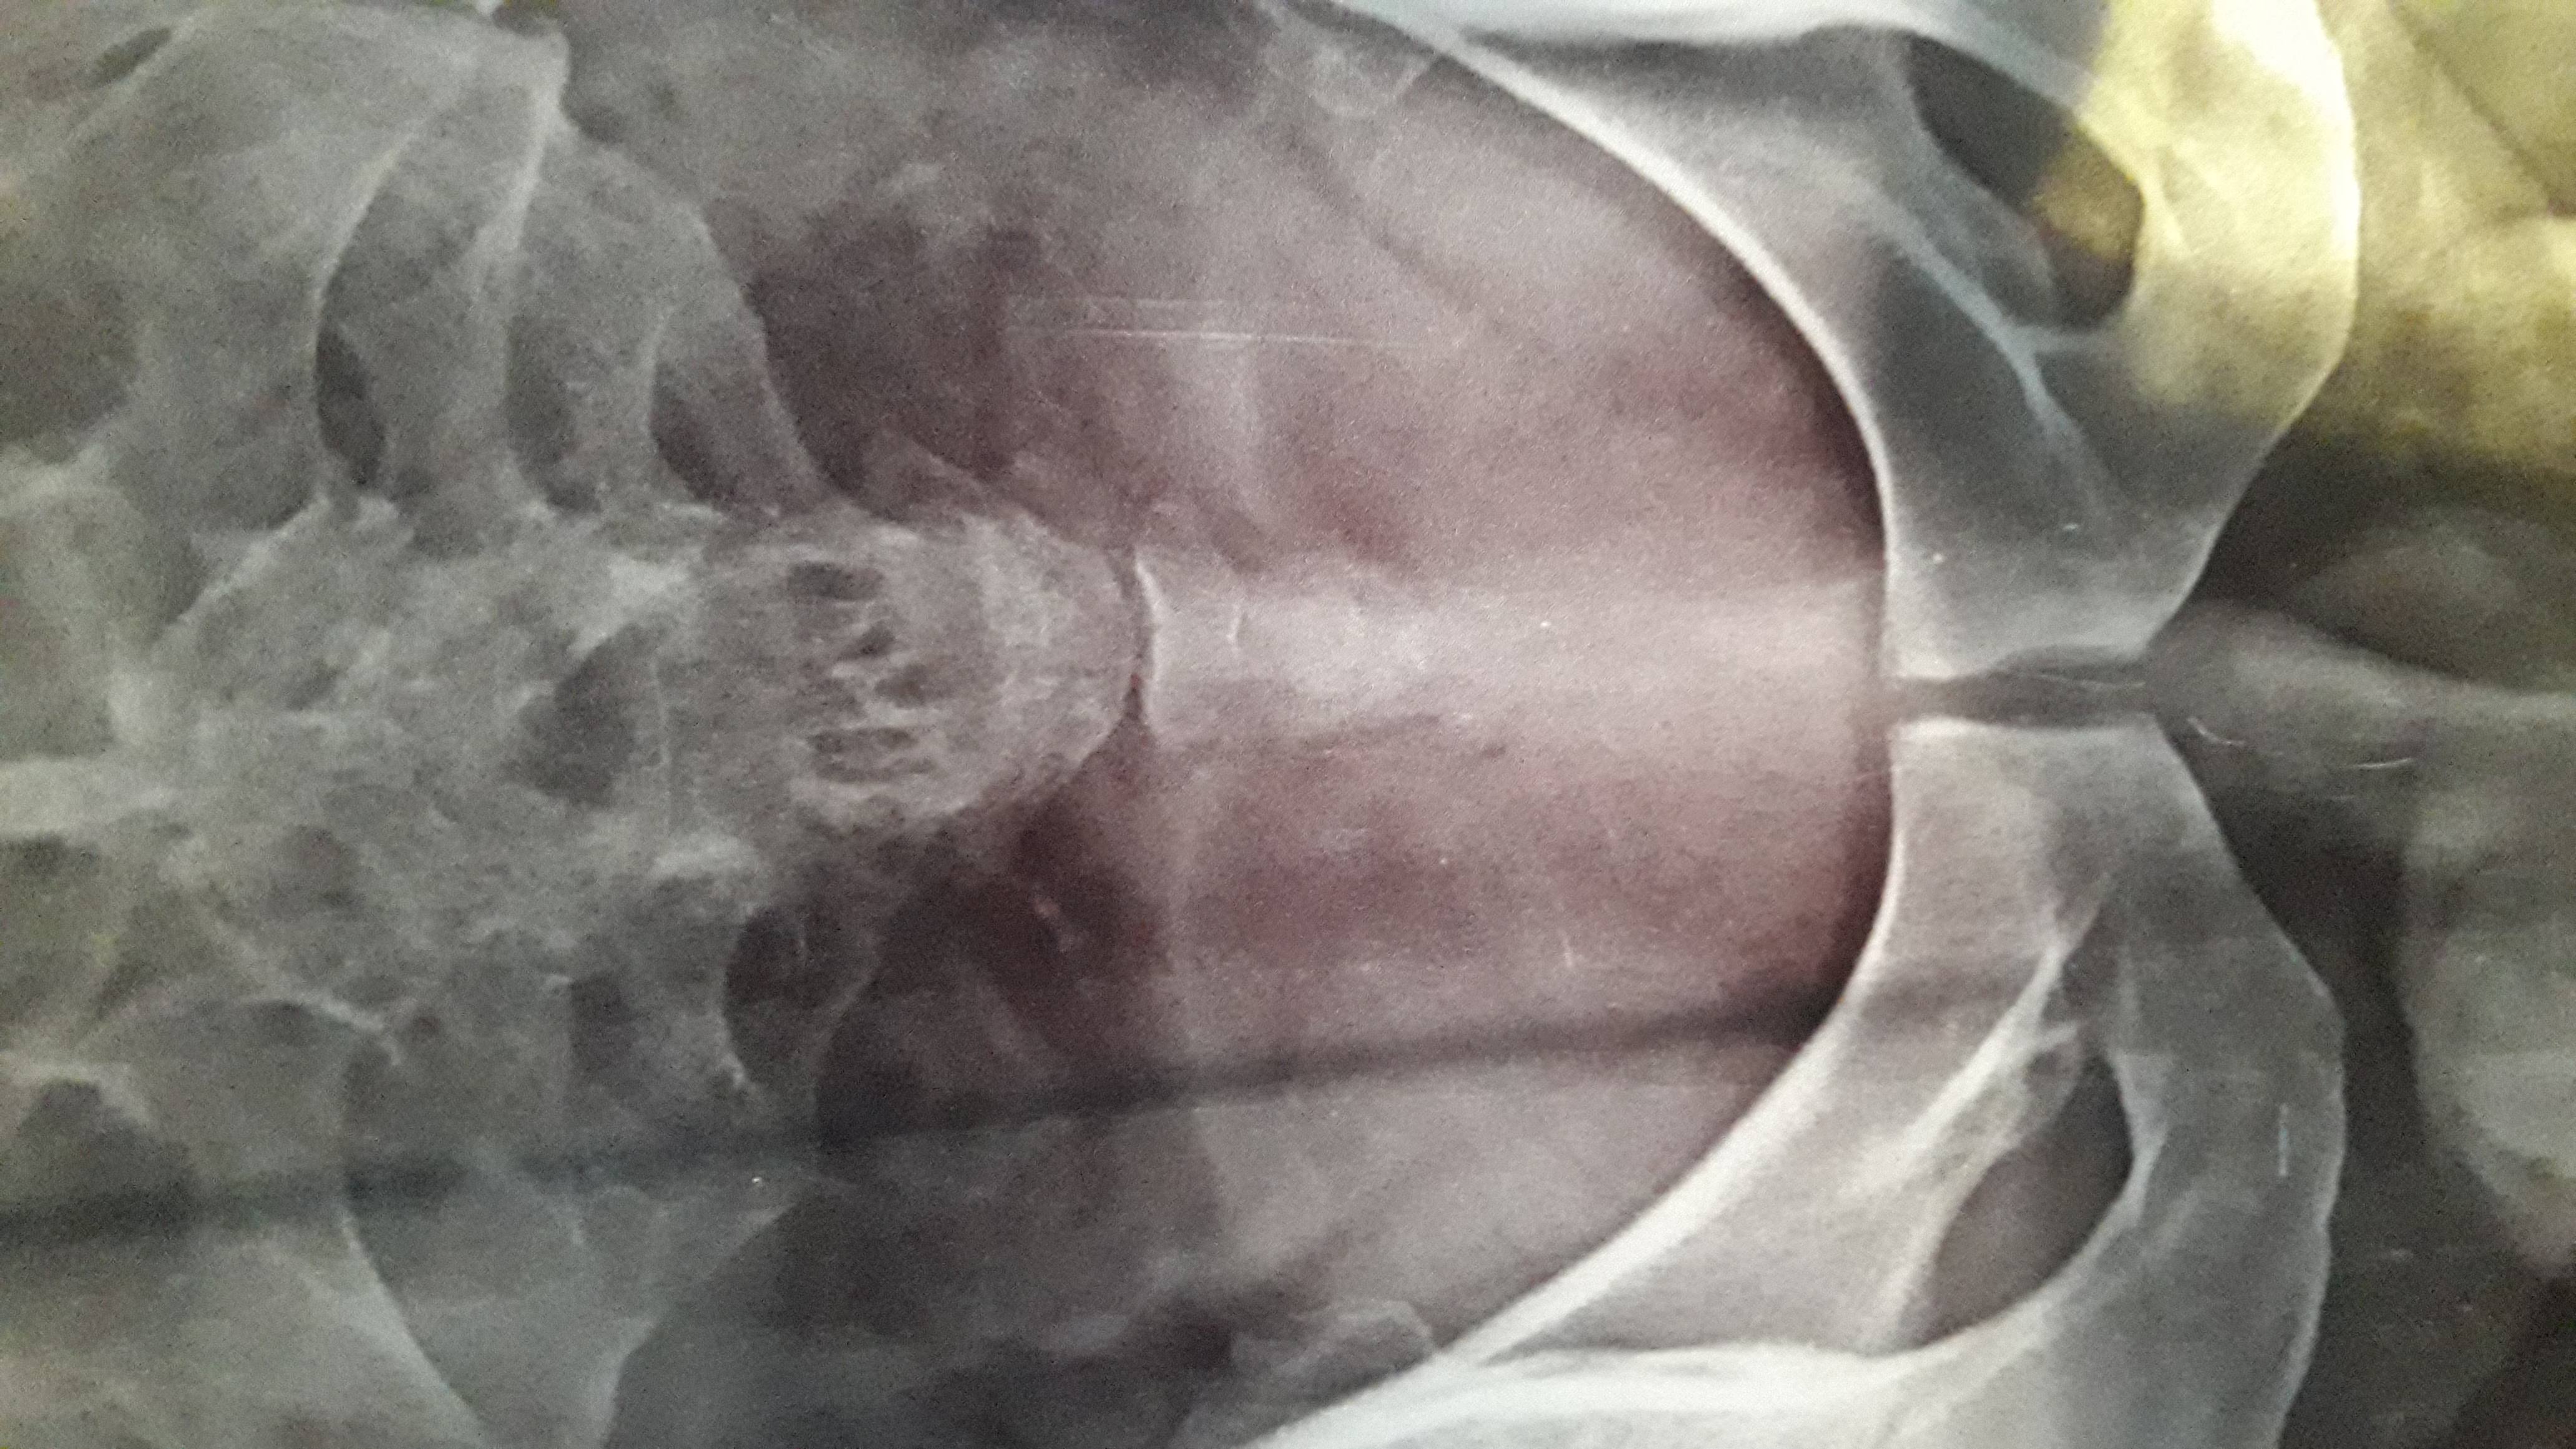

Sir, Is images me coccyx me fracture hai kya plz inform me